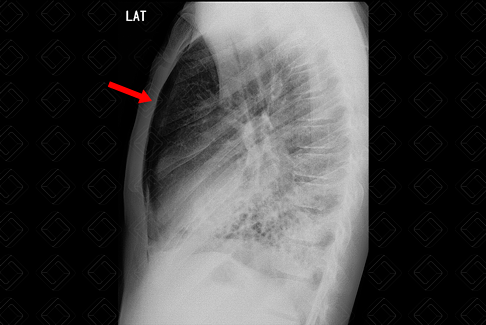

Descrição das figuras 3 e 4: Paciente portador da síndrome de Kartagener ( situs inversus e com bronquiectasias na base direita). Radiografia de tórax evidenciando hipertransparência no ápice do pulmão direito associado a não visualização da trama vascular, compatível com pneumotórax. No estudo em perfil, fica bem evidente o pneumotórax (seta vermelha).